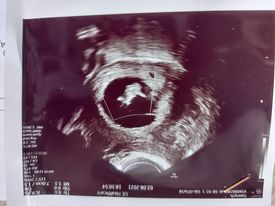

Czesc jestem tu od tygodnia i wiele dobrych słow usłyszałam od dziewczyn i porad.Nietety okazało sie najgorsze.Byłam potwierdzic prywatnie u innego lekarza co dzieje sie z ciążą.Jestem w 7tyg. i p.doktor powiedzial,że nie widzi serduszka i bardzo mu przykro bo ciążą nie żyje.Dał mi skierowanie na zabieg.Jak to wszystko wygląda i jak długo sie jest w szpitalu.Czego mam sie spodziewac? Narazie probuje sie oswoić z tą myślą ,że dzidziuś sie nie rozwinął.Strasznie mi cieżko pierwszy raz jestem w takiej sytuacji.To moja druga ciąża.Może juz wiek juz niestety nie ten i dac sobie spokój.Ilona 40lat. :,(

• 7tydzień.jpg

7tydzień.jpg

11,6 KB · Wyświetleń: 136

A masz regularne miesiączki? Badałaś betę? Jaka jest wielkość zarodka? Niestety te zdjęcia są zbyt małe i nie jestem w stanie tego zobaczyć. Nie chcę Cię na nic nastawiać, ale moim zdaniem lekarz się trochę pospieszył z tym skierowaniem.